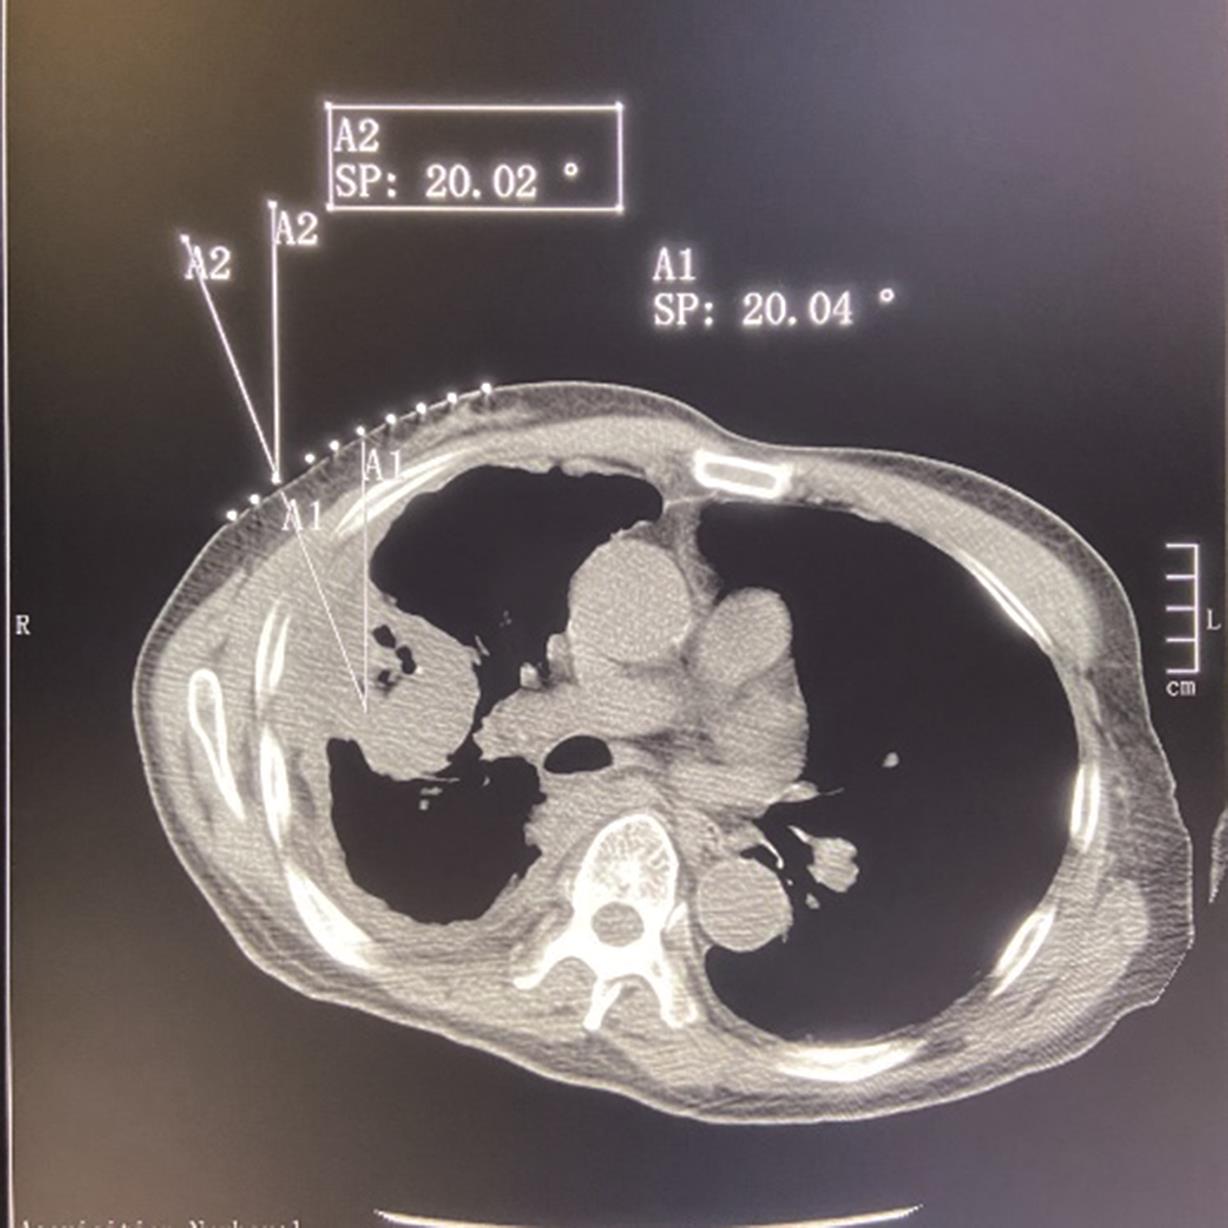

• 靶点靶线体表描记法在CT引导经皮肺穿刺活检术中的应用

2023, 48(9):1133-1137. DOI: 10.13406/j.cnki.cyxb.003328

摘要 (93) HTML (23) PDF 2.14 M (224) 评论 (0) 收藏

摘要:目的 旨在探讨靶点靶线体表描记法在CT引导经皮肺穿刺活检术中的技术要点及应用价值。方法 选取2021年8月至2022年4月进行肺穿刺活检的病例152例,随机分为A组(77例,采用靶点靶线体表描记法穿刺)和B组(75例,常规穿刺法),比较2组首次进针成功率、CT扫描次数、诊断准确率、术后并发症及手术时间以评估2种手术方法效果。结果 2组均穿刺成功并取得标本,穿刺成功率均为100%。首次进针成功:A组64例,B组62例,2组间无统计学差异(χ=0.005,P=0.941);CT扫描次数超标:A组18例,B组54例,2组间有统计学差异(χ=36.030,P<0.05);诊断准确:A组70例,B组68例,2组间无统计学差异(χ=0.003,P=0.959);咯血:A组12例,B组9例,2组间无统计学差异(χ=0.410,P=0.522);气胸:A组10例,B组11例,2组间无统计学差异(χ=0.090,P=0.764);手术时间:A组平均(19.88±4.47) min,B组平均(32.23±4.95) min,2组间有统计学差异(t检验,P<0.05)。结论 CT引导肺穿刺术中应用靶点靶线体表描记法简单易行,能准确指导CT引导肺穿刺术中穿刺角度的把握,减少术中CT扫描次数,值得在临床中推广。